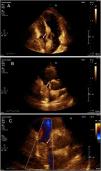

A 45-year-old female with no past medical history presented to the hospital with six months of dry cough, associated with diffuse abdominal pain and lower extremity edema. On physical examination, grade two lower extremity edema and ascites were found. The results of the laboratory tests demonstrated elevated Ca-125. Abdominal tomography was performed showing left complex adnexal mass and lobulated hepatic mass with compression and displacement of inferior vena cava and right atrial extension (Figure 1A and 1B). Transthoracic echocardiography documented echo-dense mass of 32 mm×31 mm, area 9.8 cm2, suggestive of intracavitary right atrial thrombus (Figure 2A, 2B and 2C, Video 1A-1C in supplemental material), left ventricular ejection fraction and diastolic function were normal and the valves had no pathologic changes. Cardiac magnetic resonance was not performed. Additionally, Holter electrocardiogram recorded atrial tachycardia. Anticoagulation was initiated. Left oophorectomy was performed based on results of diagnosis of serous ovarian carcinoma. Liver, neck and bone metastatic disease was observed. Chemotherapy with carboplatin and paclitaxel was started. Currently, patient is receiving the second cycle of chemotherapy, symptoms have been relieved without cardiovascular events. Control images will be performed after chemotherapy has been completed to assess therapy response.

A: Transthoracic echocardiography showing echo-dense mass of 32 mm×31 mm, area 9.8 cm2 within right atrium suggestive of mass or intracavitary thrombus (white arrow). C: Transthoracic echocardiography showing mass within right atrium (white arrow). B: Transthoracic echocardiography showing restriction to color flow Doppler (white arrow).